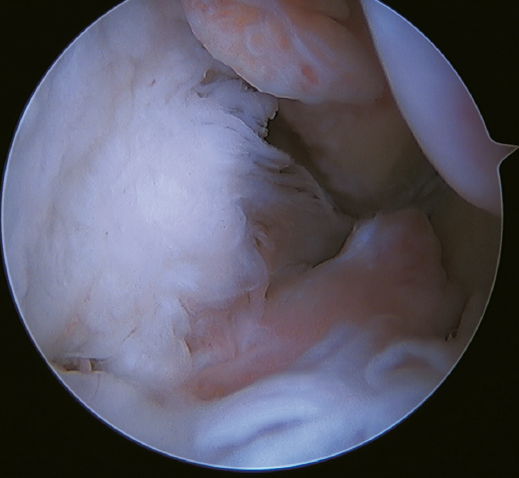

Rotational instability is a relatively novel concept introduced in 2011 by Buchhorn(67), describing combined injuries of the lateral complex and deltoid ligament, and an anatomical reconstruction technique for both injuries. Although there is no biomechanical evidence as to why medial injury occurs in patients who have not suffered eversion trauma, it is likely that the stress maintained on the medial complex in lateral instability may evolve into rotational instability - which is in line with the previously commented domino effect theory (5,62). It is estimated that up to 10-15% of all cases of CLAI may progress to injury of the medial complex, especially affecting its most anterior fibers. Recently, Vega(68) described the combination of injuries of the lateral complex with the "book-page" injury (Figure 7) of the superficial tibiotalar fascicle of the deltoid ligament, due to excessive internal rotation in chronic lateral instability, and its treatment through direct repair of both lesions. Acevedo(34) and Vega(68) also described the safety position of the anchors in the medial malleolus.